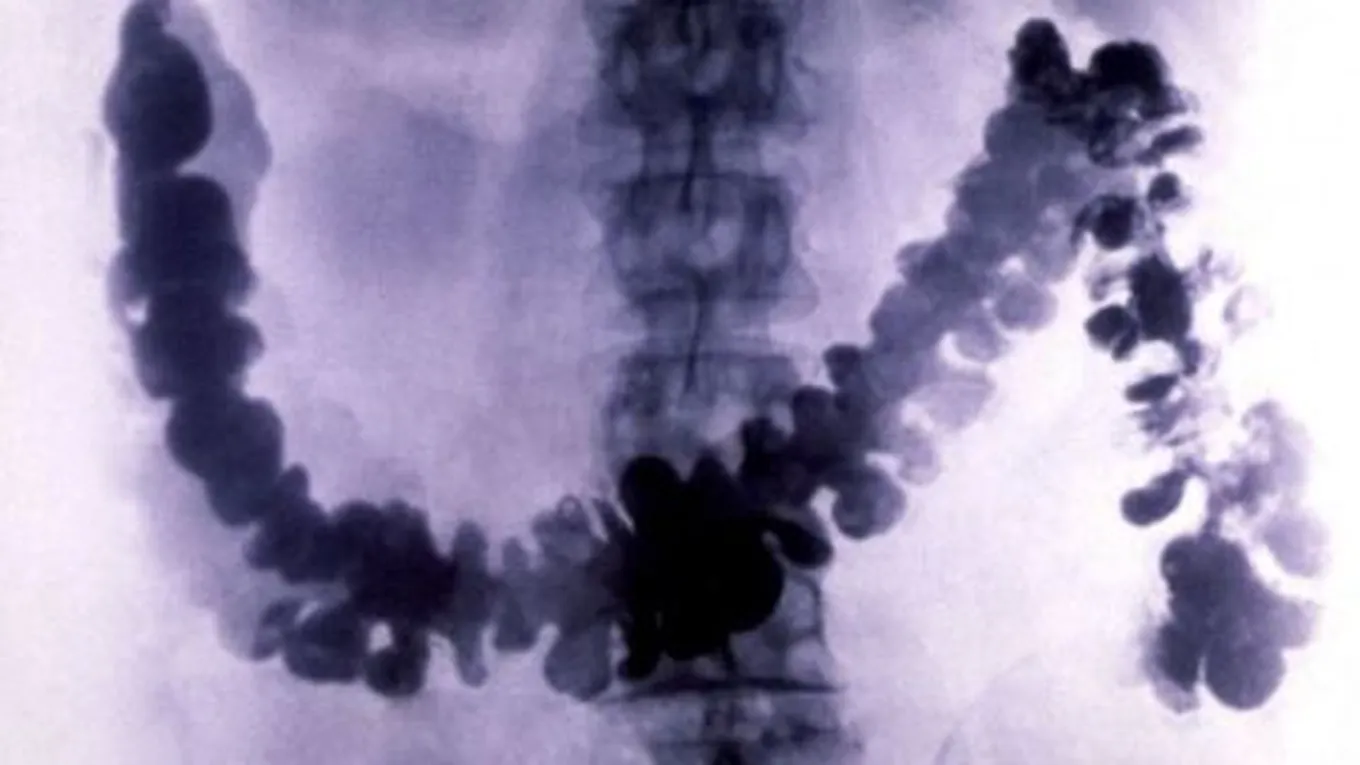

يُعرّف تضخّم القولون (بالإنجليزية: Megacolon) بحدوث تمدّد غير طبيعيّ في القولون، ويتمّ استخدام مصطلح تضخم القولون السميّ (بالإنجليزية: Toxic megacolon) للتعبير عن خطورة هذه الحالة، وعلى الرغم من أنّ مشكلة تضخّم القولون تُعدّ من الحالات الصحيّة النادرة إلّا أنّها قد تكون مهدّدة لحياة الشخص المصاب، وتتمثل هذه المشكلة بالتهاب وانتفاخ الطبقات الداخليّة للقولون ممّا يؤدي إلى توقف عمل القولون، وفي بعض الحالات الشديدة قد يحدث تمزّق في القولون، والذي بدوره قد يؤدي إلى تعفّن الدم (بالإنجليزية: Sepsis) والوفاة.[1][2]